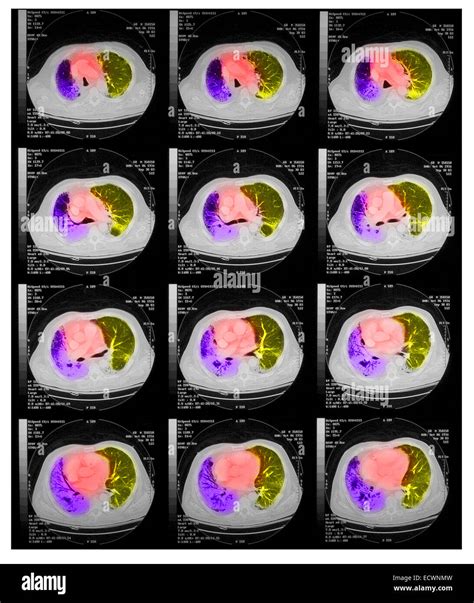

When a respiratory infection lingers or becomes severe, healthcare providers often look for more detailed imaging than a standard chest X-ray can provide. This is where a Pneumonia CT Scan becomes a critical diagnostic tool. Unlike a traditional X-ray, which produces a two-dimensional image, a computed tomography (CT) scan creates detailed, cross-sectional views of the lungs. This allows doctors to visualize the extent of inflammation, identify complications like abscesses or pleural effusions, and accurately differentiate pneumonia from other lung conditions. Understanding when and why this imaging procedure is necessary can help patients better navigate their diagnostic journey.

Undergoing a Pneumonia CT Scan is generally a quick and painless process. It is a non-invasive procedure that uses specialized X-ray equipment combined with advanced computer processing to generate images. Here is what typically happens during the scan:

3. The Scan: The scanner will move around you, taking multiple images from different angles. You will likely be asked to hold your breath for short intervals to prevent movement blur.

Once the scan is completed, a radiologist will interpret the images and generate a report. When viewing a Pneumonia CT Scan, medical professionals look for specific patterns of lung involvement. These patterns often indicate the type of pneumonia or the severity of the inflammatory response.

Common findings often described in reports include:

• Consolidation: This refers to the filling of air spaces (alveoli) with fluid, pus, or other material, appearing as dense, white areas on the scan.

• Ground-Glass Opacity (GGO): A hazy appearance in the lungs, indicating partial filling of air spaces or thickening of the lung interstitium. This is often seen in viral pneumonias.

• Bronchograms: The appearance of air-filled bronchi surrounded by consolidated lung tissue.

• Pleural Effusion: The buildup of fluid in the space between the lung and the chest wall.

• Nodules or Cavitation: These findings may prompt further investigation to rule out other infections or malignancy.

It is important to remember that these findings must always be correlated with the patient's symptoms, laboratory results, and clinical history. A report with "positive findings" does not always imply a worst-case scenario, as many patterns are typical of common bacterial or viral infections.